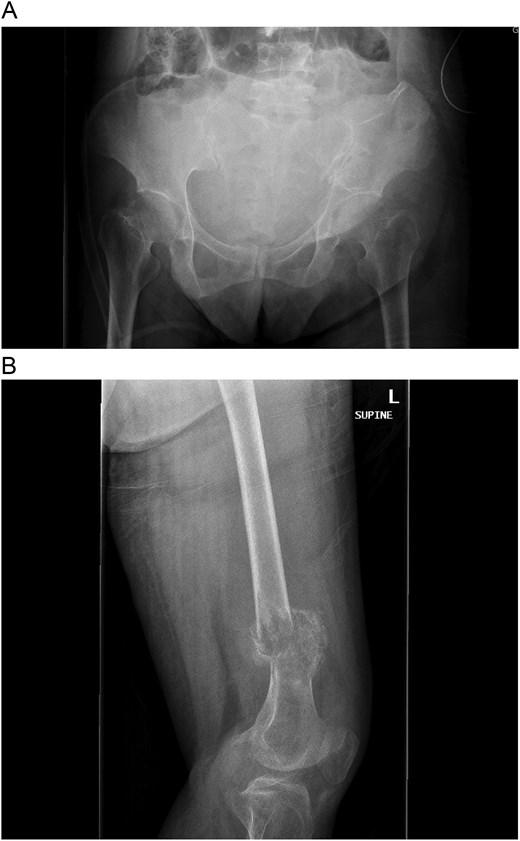

A 30-year-old pregnant woman (G2A1) presented at 32 weeks’ gestation with hypertension and left thigh pain, unable to weight-bear for a week. Initial workup included an ultrasound to rule out deep vein thrombosis and radiographs, which showed an aggressive lesion in the distal femur with periosteal reaction (Fig. 1A and B). She was referred to orthopedic oncology, and a biopsy was arranged. Routine blood tests revealed markedly elevated serum calcium of 4.13 mmol/L (normal: 2.10–2.60 mmol/L). Histopathological analysis showed multinucleated giant cells, but radiographs were inconsistent with giant cell tumor (GCT), raising concern for a malignant lesion. Further investigation confirmed primary hyperparathyroidism, prompting consideration of a brown tumor. The patient was referred to head and neck surgery for parathyroidectomy evaluation.